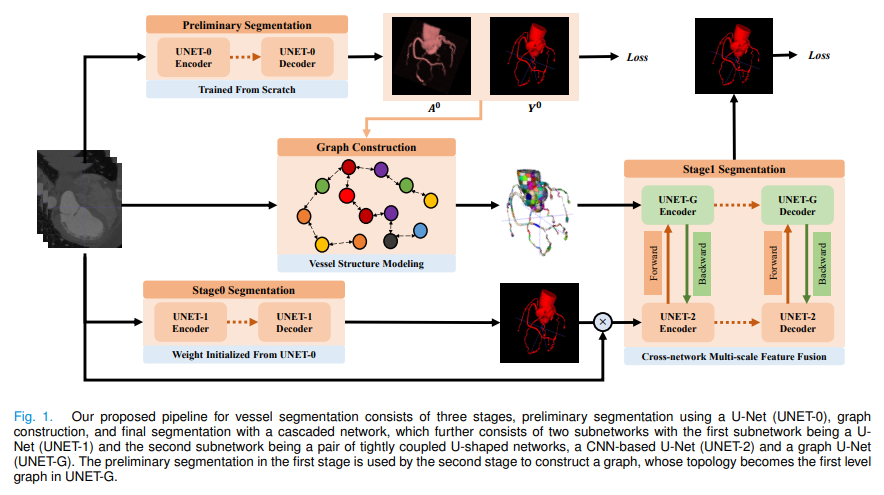

图卷积,跨网络多尺度特征融合,用于血管分割。

血管分割被广泛用于帮助血管疾病的诊断。使用现有方法重建的血管往往不够准确,无法满足临床使用标准。这是因为三维血管结构非常复杂,并表现出独特的特征,包括稀疏性和各向异性。在本文中,我们提出了一种新型的混合深度神经网络,用于血管分割。我们的网络由两个级联的子网络组成,分别进行初始和细化分割。第二个子网络进一步有两个紧密耦合的组件,一个是传统的基于CNN的U-Net,一个是 graph U-Net。在这两个U型网络之间进行跨网络多尺度特征融合,以有效支持高质量的血管分割。整个级联网络可以从头到尾进行训练。第二个子网络中的graph 是根据血管概率图以及原始CT容积中的外观和语义相似性构建的。为了解决血管的稀疏性和各向异性带来的挑战,较高比例的graph 节点分布在可能包含血管的区域,而较高比例的边缘则是按照潜在的附近血管的方向。广泛的实验表明,我们的深度网络在多个公共和内部数据集上实现了最先进的3D血管分割性能。